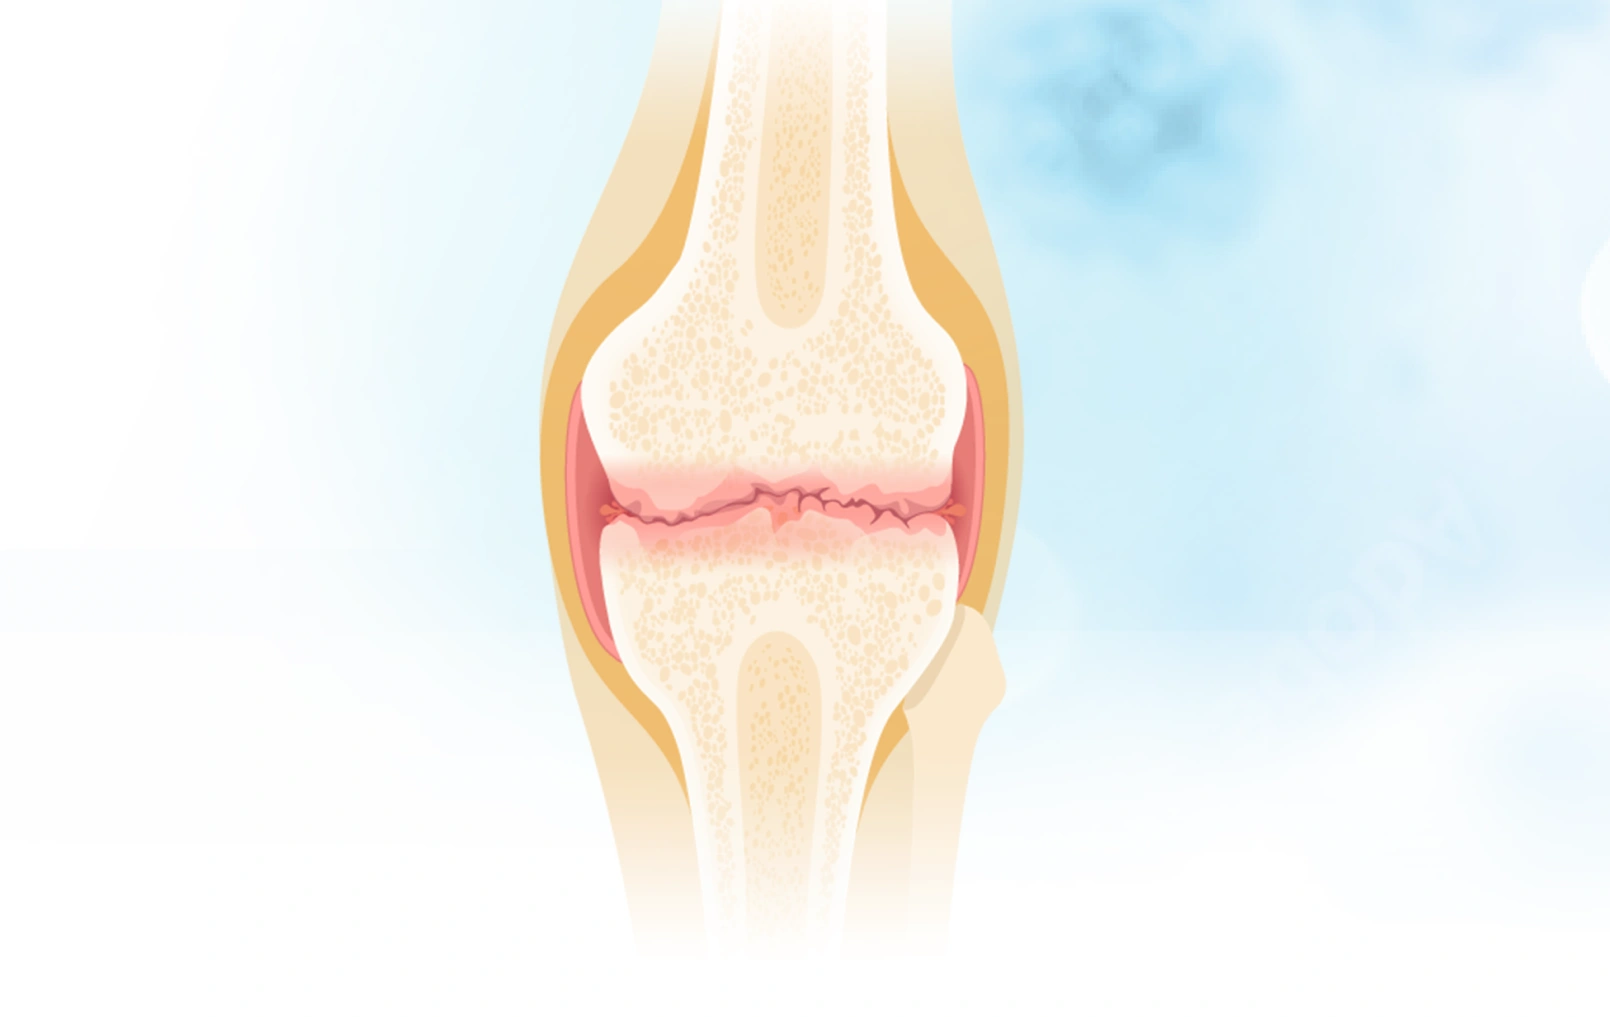

关节里的“减震器”去哪了?深度拆解骨关节炎的本质

骨关节炎不是一个突然降临的诅咒,而是长期“错误使用”身体的结果。 请记住: 软骨(减震垫)需要被温柔对待。 滑液(机油)需要通过科学运动来保持新鲜。 全...

骨关节炎的病理生理机制

你有没有想过,为什么有些人50岁就膝盖疼得上不了楼,而有些人80岁还能爬山? 为什么关节里那层看似不起眼的软骨一旦出问题,就能让一个人从"健步如飞"变成"举步...